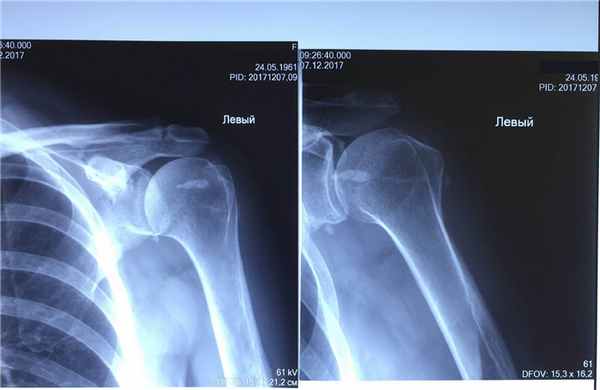

На 10 день после выполнения процедуры гидроэвакуации выполнен рентген-контроль левого плечевого сустава:

Фото 4. Рентген-снимок левого плечевого сустава пациентки после проведенного лечения.